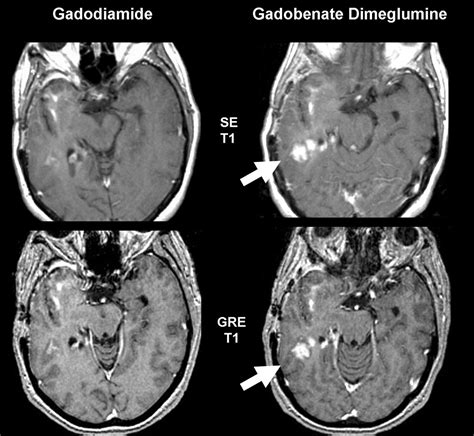

The contrast agent most commonly used in a brain MRI with contrast is a substance called gadolinium. Unlike the iodine-based contrast used in CT scans, gadolinium is generally well-tolerated and poses a lower risk of allergic reactions. When injected intravenously, this contrast material travels through the bloodstream and accumulates in areas of the brain where the blood-brain barrier—a protective network of blood vessels—is damaged or where there is increased blood flow.

By highlighting these specific areas, the contrast agent allows radiologists to distinguish healthy tissue from diseased tissue. It acts like a spotlight, making lesions, tumors, or areas of inflammation "light up" on the resulting images. Without this enhancement, subtle abnormalities might remain hidden, leading to potentially delayed or incorrect diagnoses.

• Brain tumors: To determine the size, location, and boundaries of a tumor, as well as how it responds to treatment.